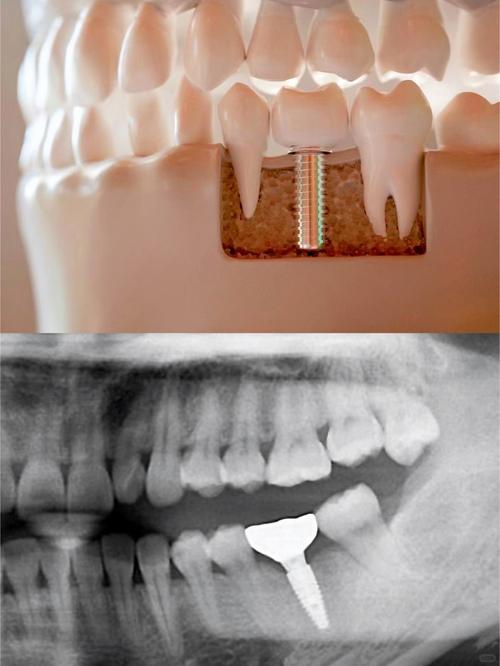

- 它通过外科手术将一个纯钛制成的金属种植体(人工牙根)植入到你的牙槽骨中。

- 等种植体与牙槽骨牢固结合(骨结合)后,在种植体上方安装一个基台,最后在基台上安装一个牙冠,看起来和功能都像真牙。